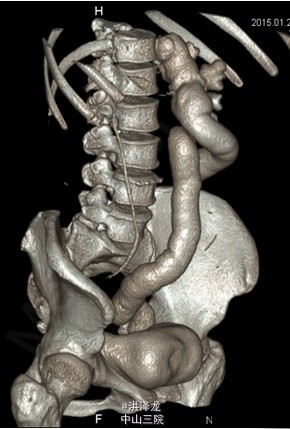

患者,女性,46岁。下腹胀痛半年。患者于6月前无明显诱因出现下腹部闷痛不适,无尿频、尿急、尿痛,无排尿困难,无血尿、脓尿,在当地医院行B超检查提示:左侧巨输尿管伴左肾 积液。现为进一步诊治收入我科。

双肾区无红肿、隆起,左肾区叩击痛(-),右肾区叩击痛(-),左侧肋脊点、肋腰点压痛(-),右侧肋脊点、肋腰点压痛(-)。腹平软,左侧输尿管走行区压痛(-),右侧输尿管走行区压痛(-),膀胱区无膨隆,压痛阴性。 CTU检查提示:左输尿管中段约平S1水平管腔稍变窄,其以下输尿管通畅,并进入膀胱内,其以上输尿管迂曲、扩张,扩张程度大致同前; 肾功能检查:左肾灌注正常,总体功能基本正常,左上尿路机械性梗阻

诊断:左侧巨输尿管。经术前准备后,行腹腔镜下左侧输尿管再植术,手术顺利,术后恢复较好。